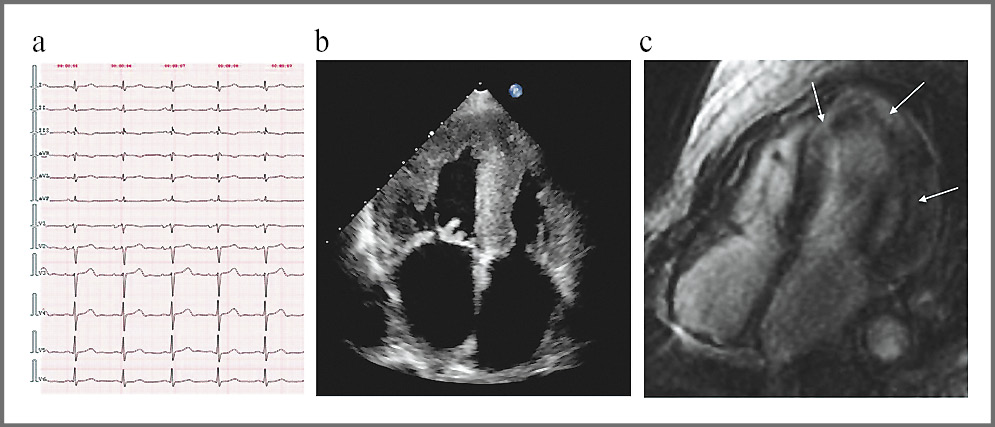

При первичном обследовании на ЭКГ регистрировались низкий вольтаж QRS в стандартных отведениях и недостаточный прирост зубца R в отведениях VI–VIII. На эхокардиограмме (ЭхоКГ) выявлены умеренная (до 16 мм) симметричная концентрическая гипертрофия миокарда левого желудочка (ЛЖ), его неоднородность, умеренное диффузное снижение глобальной сократимости ЛЖ (фракция выброса – ФВ ЛЖ 48%), тяжелое нарушение диастолической функции ЛЖ по рестриктивному типу. Диагностирована гипертрофическая кардиомиопатия (ГКМП), дифференциальный диагноз которой предполагает исключение метаболических заболеваний (фенокопий). На магнитно-резонансной томографии (МРТ) сердца – диффузное интрамиокардиальное накопление гадолиниевого контраста в базальных и срединных сегментах, а также циркулярное субэндокардиальное накопление в апикальных сегментах ЛЖ (рис. 1, a–c).

Рис. 1: a – ЭКГ; b – ЭхоКГ; с – МРТ сердца (отсроченное контрастирование, IR-последовательность с подавлением сигнала от миокарда).

Fig. 1. a – electrocardiogram; b – echocardiogram; c – magnetic resonance imaging of the heart (delayed contrast enhancement, IR sequence with suppression of the signal from the myocardium).

На основании данных ЭхоКГ и МРТ заподозрена амилоидная кардиомиопатия (АК). Анализ периферической крови и суточной мочи на моноклональную секрецию и анализ биоптата костного мозга не выявили амилоидогенный клон плазматических клеток, что позволило исключить самый частый AL-тип амилоидоза. Несмотря на проводимую терапию фуросемидом, явления сердечной недостаточности (СН) прогрессировали, и через полгода больная предъявляла жалобы на одышку при минимальной физической нагрузке (ходьба до 50 м) и в горизонтальном положении, увеличение массы тела и объема живота, общую слабость и быструю утомляемость. Компенсация явлений СН достигнута на двойной мочегонной терапии торасемидом и эплереноном. По данным повторной ЭхоКГ выявлено утолщение атриовентрикулярных клапанов, межпредсердной перегородки, значительное снижение глобальной продольной систолической деформации (стрейн) миокарда ЛЖ (до 8%) за счет базальных и срединных сегментов с сохраненной систолической функцией верхушки (верхушечный тип). На коронароангиографии значимого атеросклеротического поражения коронарных артерий не выявлено.